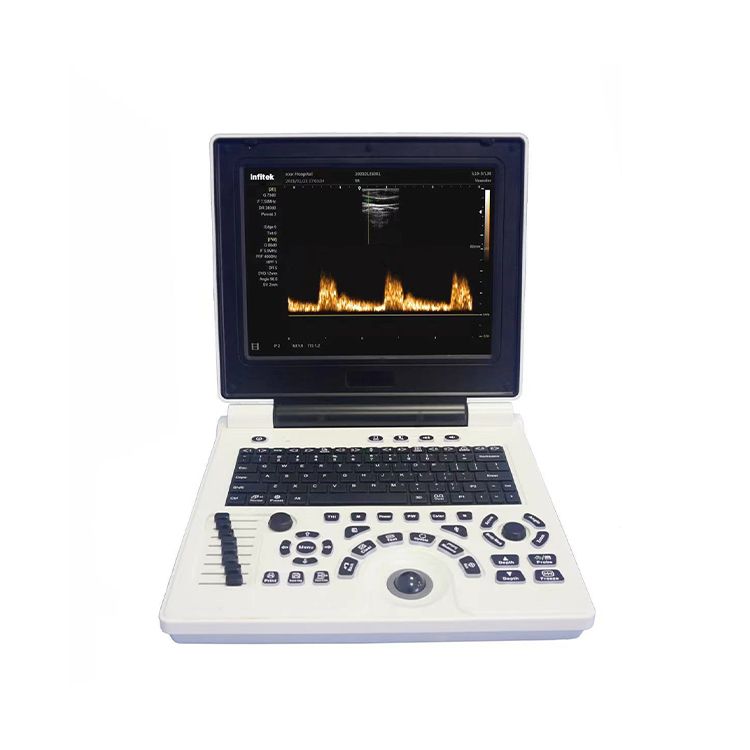

- 具有倾斜功能的高分辨率 12 英寸 LED

超声仪, 多普勒, US-HCE20

Description

1. 12英寸液晶显示屏

2. Windows 7平台操作系统

出色的人体工程学设计

1. 高分辨率12英寸LED,具有倾斜功能

2.用户友好的键盘和控件

Specifications

| 型号 | 美国-HCE20 |

| 显示 | 12寸液晶屏 |

| 操作系统 | Windows 7的 |